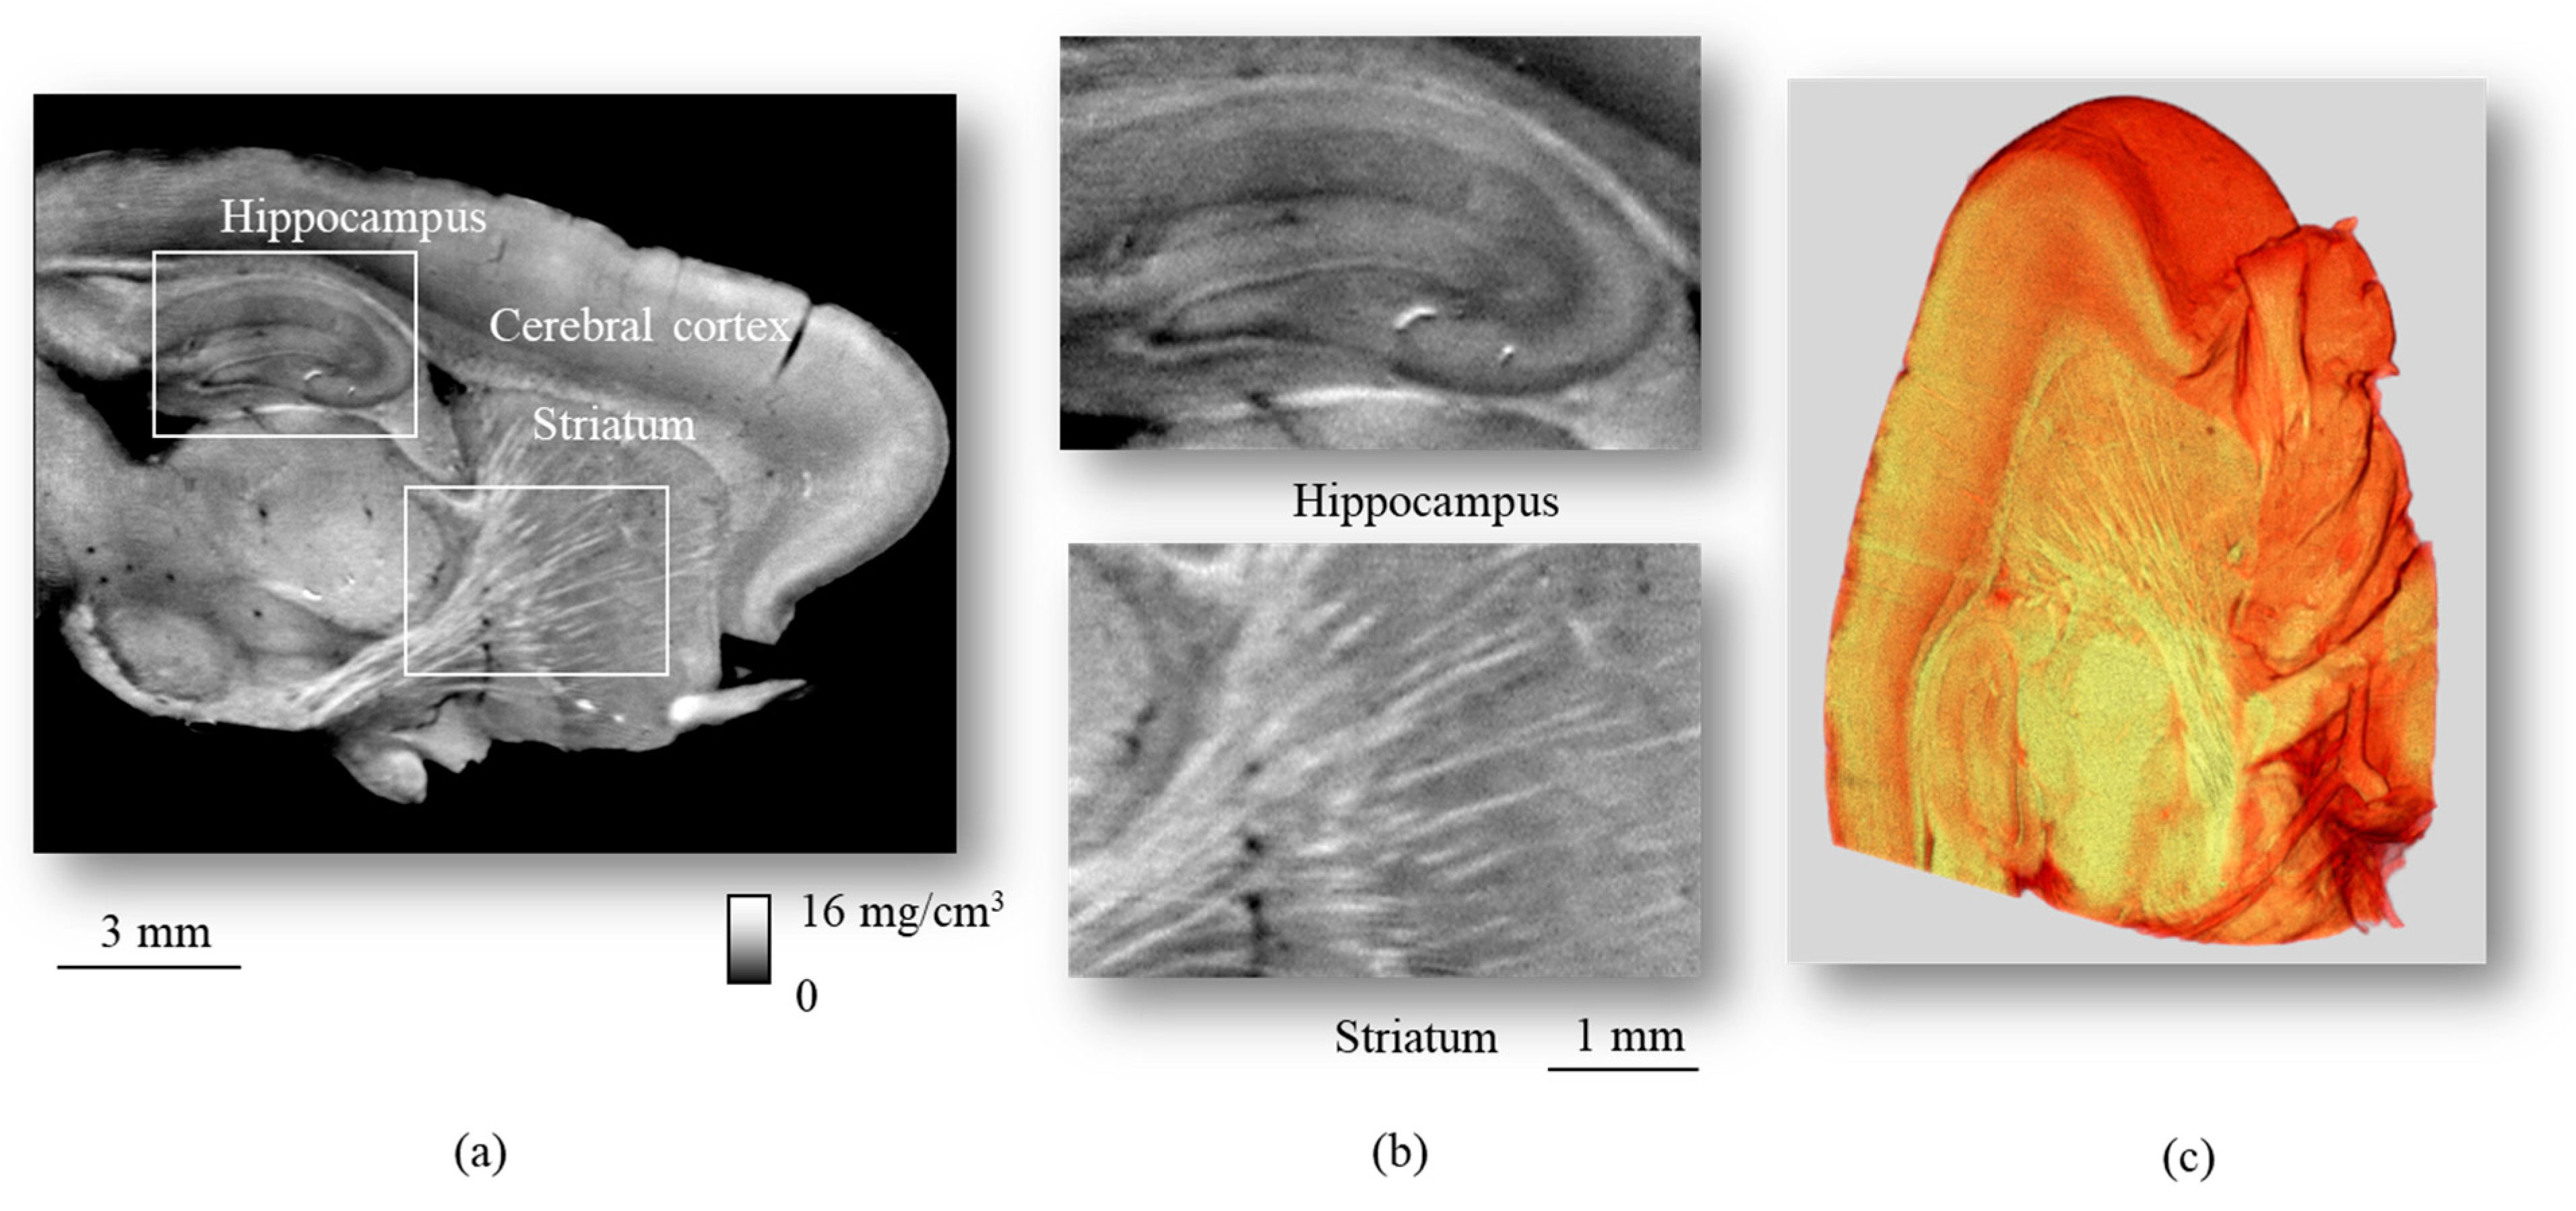

- Momose, A.; Takeda, T.; Itai, Y.; Hirano, K. Phase-contrast X-ray computed tomography for observing biological soft tissues. Nat. Med. 1996, 2, 473–475. [Google Scholar] [CrossRef]

- Lwin, T.-T.; Yoneyama, A.; Hara, A.; Ohbu, M.; Maruyama, H.; Taguchi, M.; Esashi, S.; Matsushima, T.; Terazaki, K.; Hyodo, K.; et al. Spontaneous brain tumor imaging of aged rat by crystal X-ray interferometer-based phase-contrast X-ray CT. Acta Radiol. Open 2016, 5, 205846011562695. [Google Scholar] [CrossRef] [Green Version]

- Noda-Saita, K.; Yoneyama, A.; Shitaka, Y.; Hirai, Y.; Terai, K.; Wu, J.; Takeda, T.; Hyodo, K.; Osakabe, N.; Yamaguchi, T.; et al. Quantitative analysis of amyloid plaques in a mouse model of Alzheimer’s disease by phase-contrast X-ray computed tomography. Neuroscience 2006, 138, 1205–1213. [Google Scholar] [CrossRef]